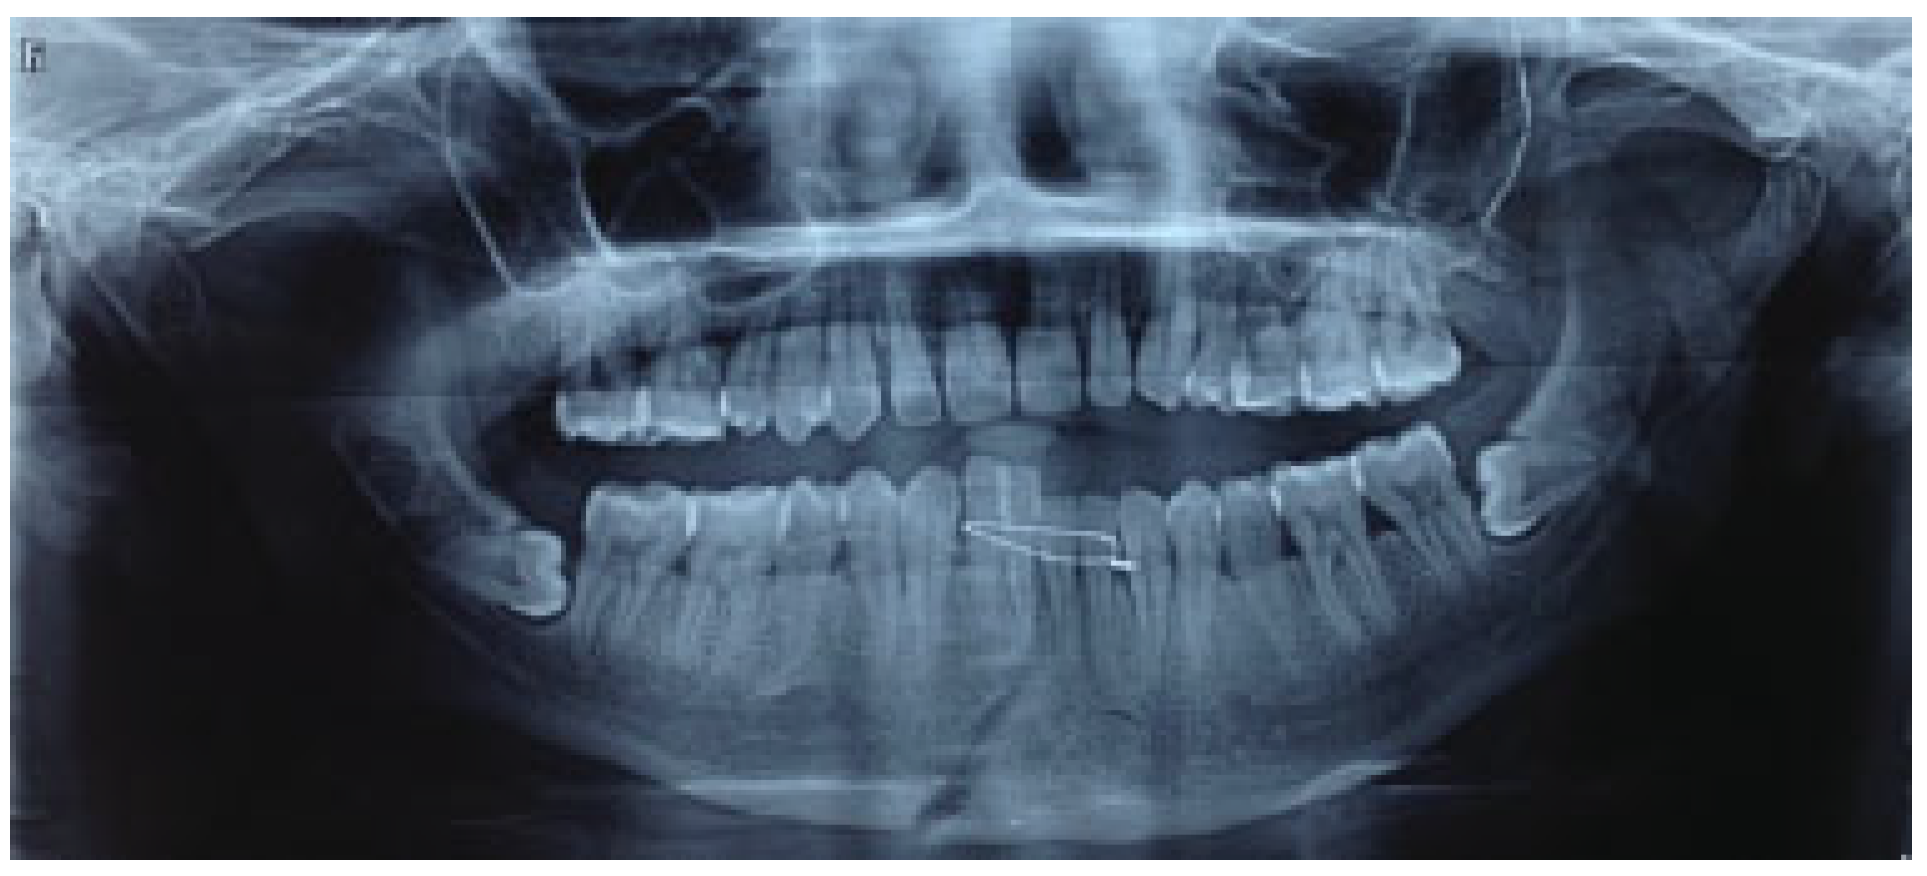

The mean for ramal height shortening was found to be 11.9 (0.99) preoperatively and 11.6 (1.57) postoperatively in Group A. It was compared using paired t-test and this difference was found not to be statistically significant (p = 0.34; Figure 1 and Figure 2). The mean for ramal height shortening was found to be 12.5 (0.84) preoperatively and (0.87) postoperatively in Group B. It was compared using paired t-test and this difference was found to be statistically significant (p < 0.05; Figure 3 and Figure 4).

Figure 1.

Group A: Preoperative orthopantomography showing left displaced subcondylar fracture and right parasymphysis fracture.